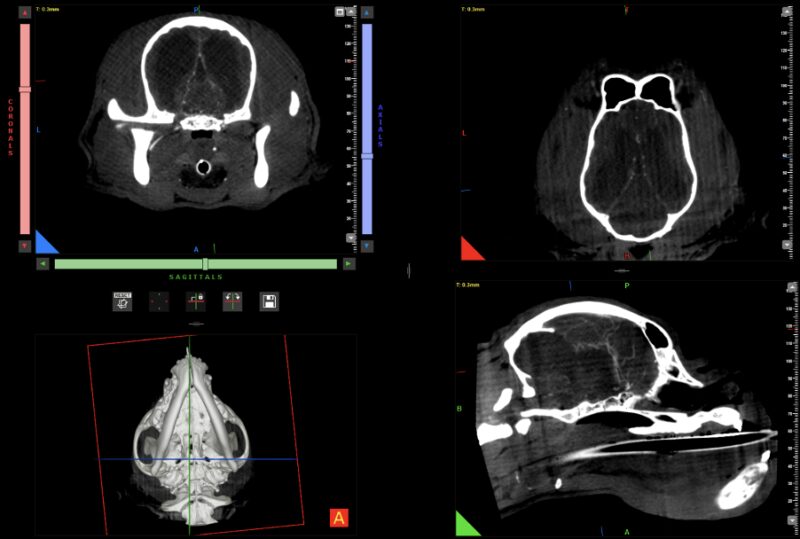

Kopf und Wirbelsäule: Auch in diesem Segment sind CBCT Einsätze aussagekräftig und erfolgreich – hier werden Scans zur genauen Diagnosestellung vom MRT abgelöst, wenn auch die zukünftige Optimierung mittels künstlicher Intelligenz die Bildqualität nochmals absehbar erhöhen wird (Abb. 7 & 8).

Ein weiterer Entwicklungsschritt ist die Integration künstlicher Intelligenz in die Bildrekonstruktion. In Zusammenarbeit mit der Firma Hawkcell verfolgen wir das Ziel, Bildqualität, Rauschreduktion und Rekonstruktionsparameter automatisiert an die jeweilige Fragestellung anzupassen. Erste Ergebnisse zeigen eine deutliche Qualitätssteigerung, in ausgewählten Anwendungen vergleichbar mit einem 16-Zeilen-Multislice-CT.

Vergleichende Darstellung eines KI optimierten Kopfscans einer Katze mit einem destruktiven Tumor im Kopfbereich (links original, rechts KI gestützt).